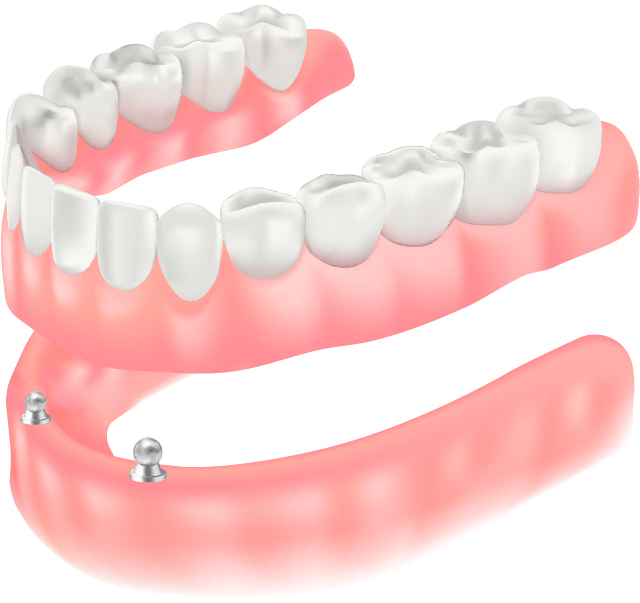

上でも説明したように、入れ歯の症例の中には、その人固有の骨や歯肉の質の問題で、どうしても入れ歯がうまく作れない場合があります。また年齢の問題で、もっと強い力で食事したいという方もいらっしゃいます。そういう場合には、入れ歯の支えとして、インプラントを用いる方法があります。

この患者様は、下の顎に2本のインプラントを用いています。インプラントの手術は30分で終了しました。写真にあるコネクターで、入れ歯をパチっと固定できます。

上で説明した、インプラントを補助的に用いる方法です。患者様のご希望や状態により、インプラントの本数やコネクターの種類は異なります。